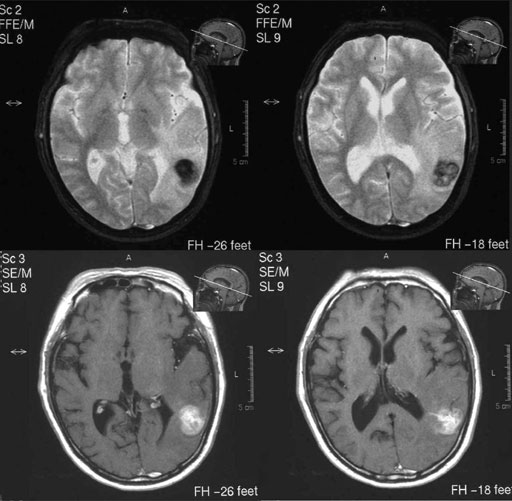

図1 MRI(T2強調像,T1強調像,FLAIR像)

図2 MRI(FFE- T2強調像,造影T1強調像)

図3 CT(単純,造影)